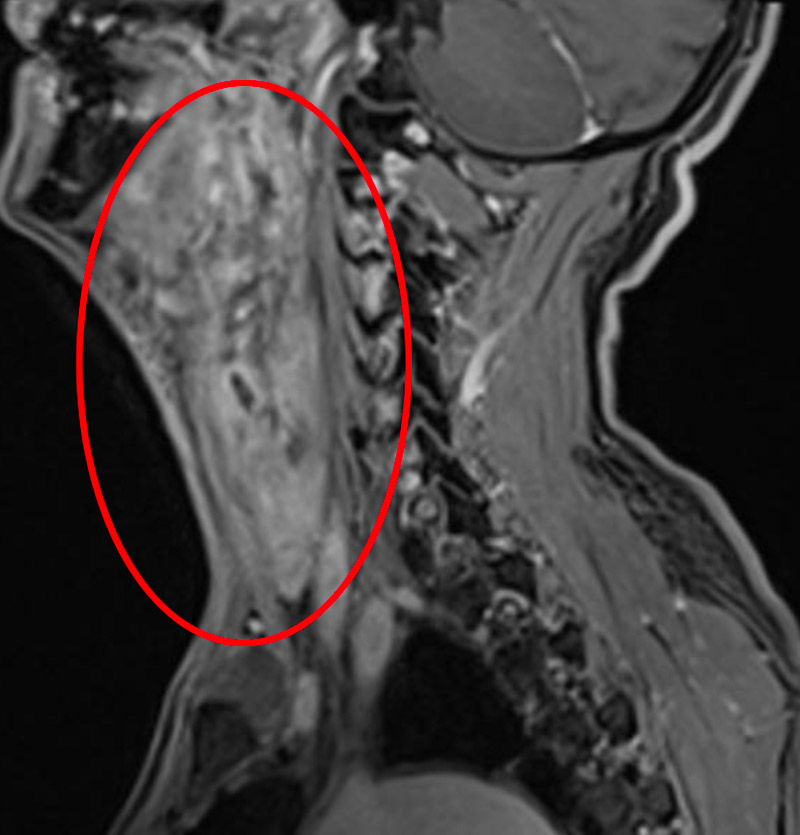

經(jīng)檢查發(fā)現(xiàn),患者喉癌已侵犯舌根、咽喉后壁、食管上端,病灶范圍廣。因放療無(wú)法控制病情,最終頭頸腫瘤MDT團(tuán)隊(duì)決定為其實(shí)施全喉切除+咽后壁、食道上段皮瓣修復(fù)術(shù)。

手術(shù)如期進(jìn)行,耳鼻咽喉科手術(shù)團(tuán)隊(duì)術(shù)中仔細(xì)分離切除腫瘤,取胸部復(fù)合肌皮瓣組織,同時(shí)修復(fù)患者頸部皮膚、下咽和食管上段缺損。這樣一來(lái),既保證了患者正常的飲食功能,又保證了患者的頸部外觀。